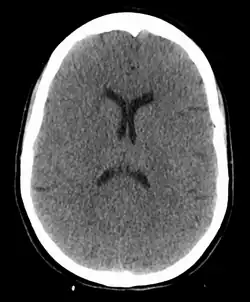

Anoxic brain injury following a hanging—both the loss of visible differentiation between grey and white matter and the reduced ventricle size due to brain swelling are visible

A hanging may induce one or more of the following medical conditions, some leading to death: